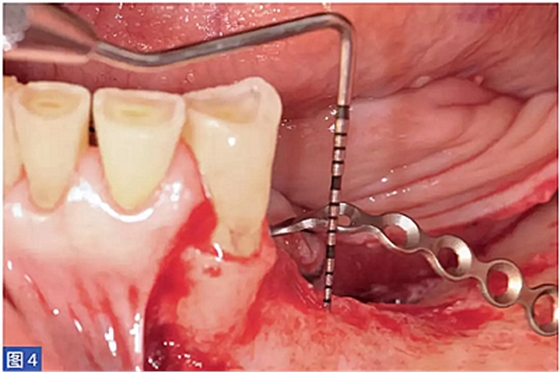

在整個(gè)手術(shù)過(guò)程中以及術(shù)后12 個(gè)月都要評(píng)估并發(fā)癥的發(fā)生。在術(shù)后12 個(gè)月,患者都要通過(guò)視覺(jué)模擬量表(VAS)對(duì)手術(shù)的滿意度從0(非常不滿意)到10(非常滿意)進(jìn)行評(píng)估。這些問(wèn)題針對(duì)對(duì)于治療過(guò)程的主觀評(píng)價(jià)。圖1-12 顯示了兩個(gè)典型病例的手術(shù)。

圖4:病例1. 術(shù)中內(nèi)固定鈦板。